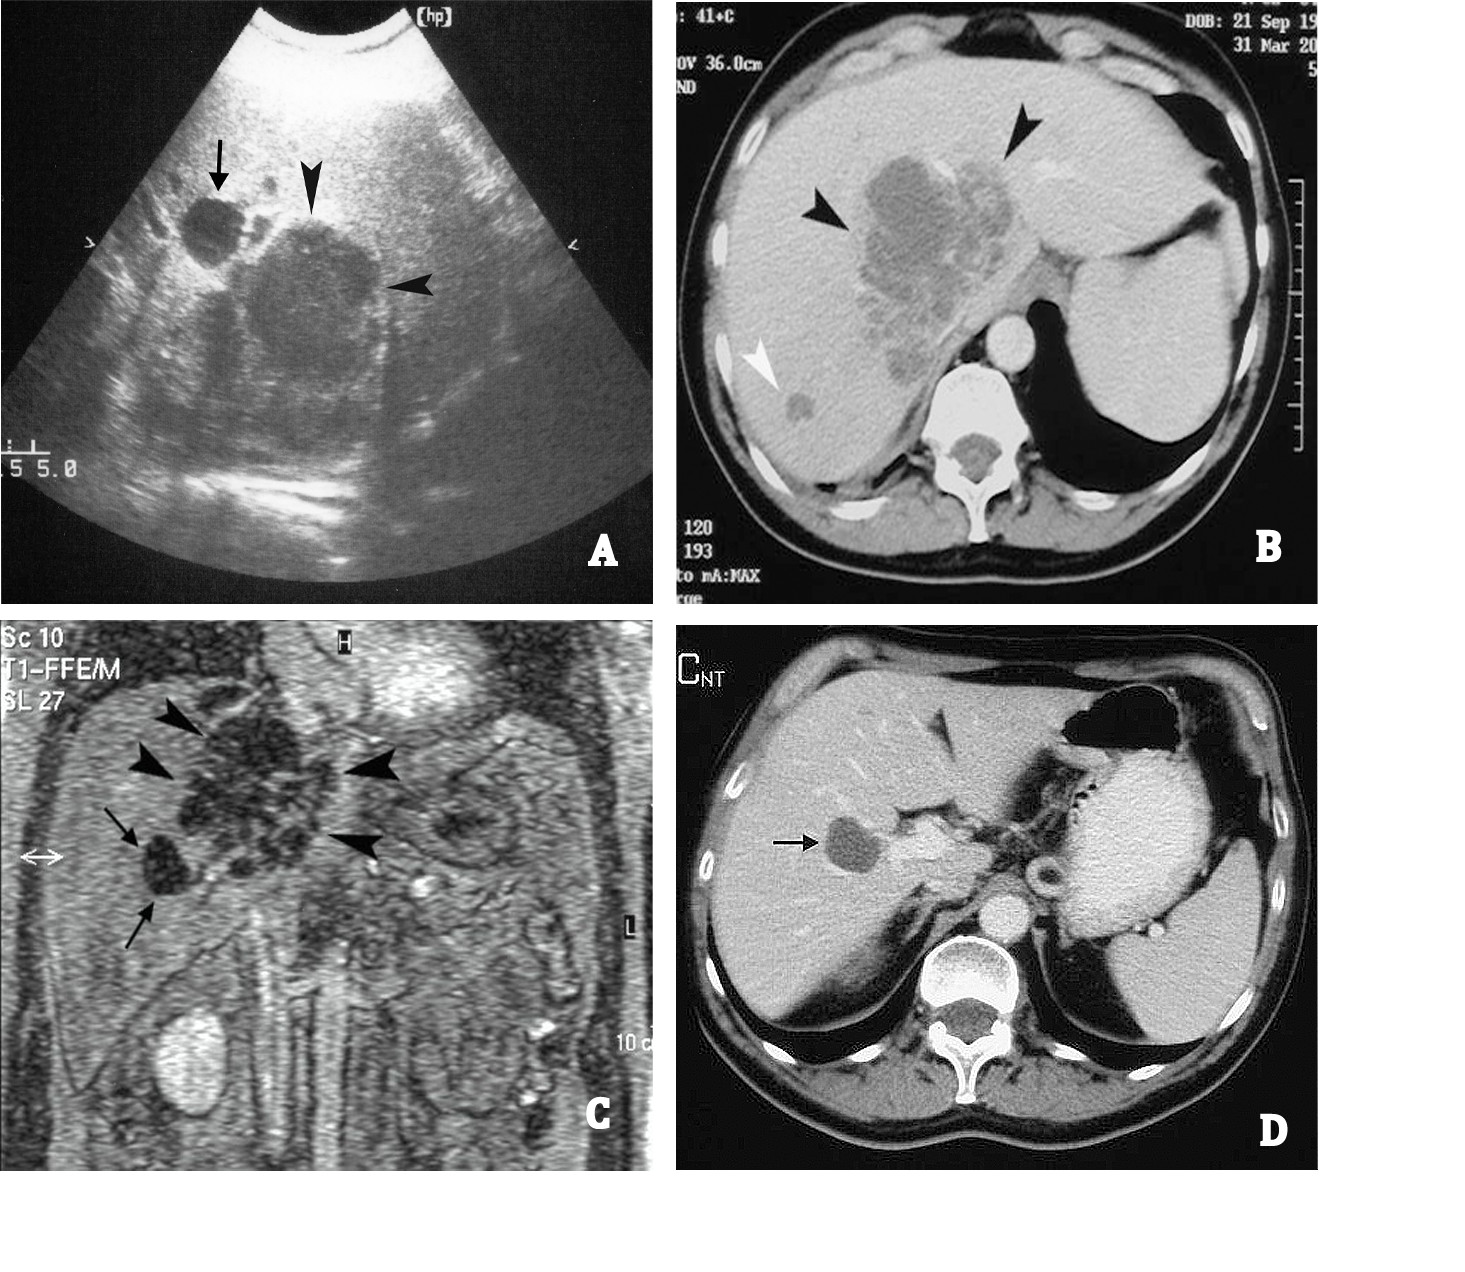

Blood test was negative for HIV, HCV, HBV, and other hepatotropic viruses. Six haemocultures collected over two consecutive days, as well as chest radiography, resulted negative. Abdominal US revealed a liver lesion of approximately 10 cm in diameter, with irregular form and poorly defined margins, located in the lateral section of the right liver lobe, close to the vena cava. No intra-hepatic or extra-hepatic biliary dilatation was observed. The liver, spleen, pancreas, and kidneys were of normal size. Spiral CT confirmed the low-density liver area slightly enhanced at the early phase after injection of a contrast medium. Also, the T2-weighted magnetic resonance images (MRI) confirmed the mass with high signal intensity and with slight enhancement at the early phase after gadolinium administration. All three imaging techniques gave rise to the suspicion of a necrotic sepimented area or neoplastic liver lesion. Furthermore, two other small lesions with similar density to the above were identified in liver segments 5 and 7. An anechoic ovalar lesion, close to the largest lesion, referable to a simple liver cyst was also detected (Figs. 1A, B and C).

Figure 1.

A. US shows a large hypoechoic lesion with ill-defined margins (black arrow heads) and an anechoic lesion (black arrow). B. Abdominal spiral CT reveals a hypointense area that was slightly enhanced in the periphery and in septations after contrast administration (black arrow heads) and a small lesion with similar density (white arrow head). C. MRI reveals a large sepimented lesion (black arrow heads) and a small hypointense lesion referable to a liver cyst (black arrows). D. A contrast-enhanced CT carried out 20 days after the discharge shows a hypointense lesion referred to a liver cyst (black arrow) and a complete resolution of the abscess.

Ten days later, the US revealed a liver lesion of approximately 3 cm in diameter and the febricula was still present. Two other US-guided needle (Chiba 18 G) aspirations of the liver lesion collected 30 and 20 mL of pus, respectively, on day 20 and 30 and the fever disappeared. The flogistic parameters (ESR, CRP, etc.,) also returned to normal values, and the patient was discharged with instructions to continue antibiotic treatment for a total of 30 days. Abdominal US and CT carried out 20 days after discharge revealed complete resolution of the liver lesion. A follow up visit, 6 months after discharge, showed the patient in good health (Fig. 1D).